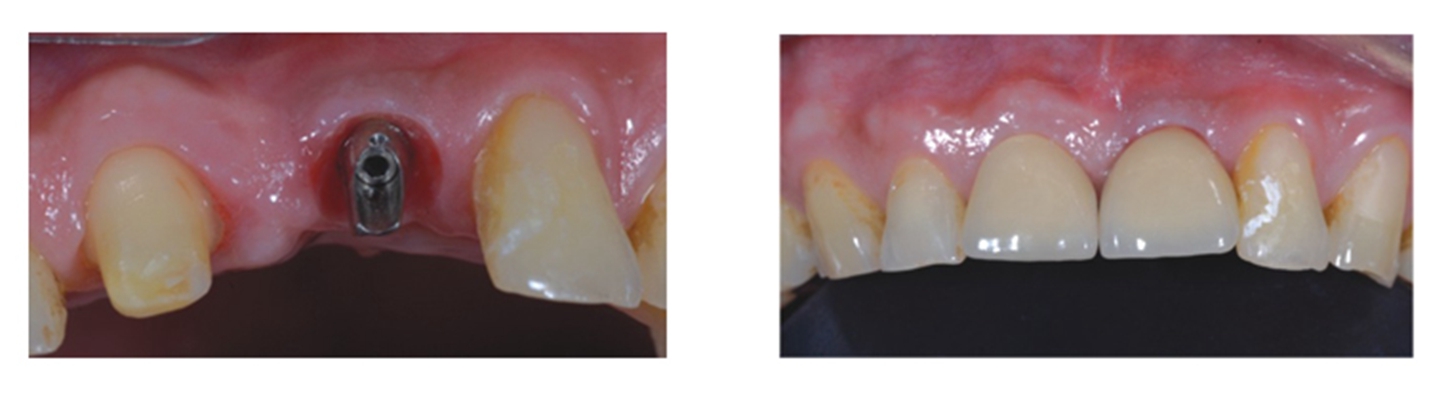

典型干槽症图片早期症状拔完智齿后伤口发白算是干槽症吗